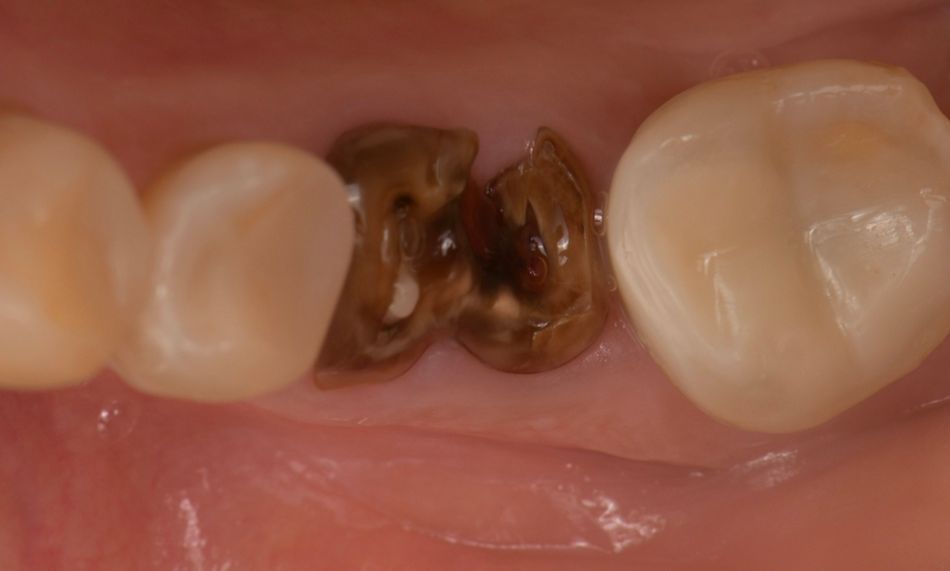

Intraoral examination revealed a root remnant of tooth #36, previously endodontically treated, showing secondary caries and a Grade III furcation involvement (Fig. 1).

Fig. 1

Radiographic and CBCT evaluation confirmed a vertical root fracture and failure of the previous endodontic treatment at tooth #36. Sufficient vertical and horizontal bone dimensions were observed, with D2 bone quality, indicating favorable conditions for immediate implant placement. The remaining teeth exhibited stable periodontal support and no significant bone loss (Fig. 2).

Fig. 2